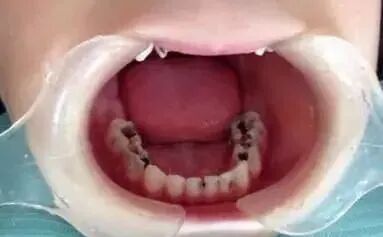

孩子乳牙患龋,家长是怎么处理的呢? 这个问题在大多数人眼里 都不能算个事儿 “反正孩子早晚要换牙的,没事啊!” 很多家长对这句话坚信不疑 这应该迄今为止“洗脑”最成功的“名言”! 然而孩子却都遭了大罪?

以上的案例仅仅是我们所看到的千万分之一二,据最新发布的全国口腔调查流行病数据显示,5 岁儿童乳牙龋患率为 70.9%。1个小孩子里, 7 个有蛀牙,可能还有 2 个正在龋齿的路上。 龋齿的危害:孩子出现蛀牙花钱事小,如果没有及时治疗,龋齿可能会危害一生: